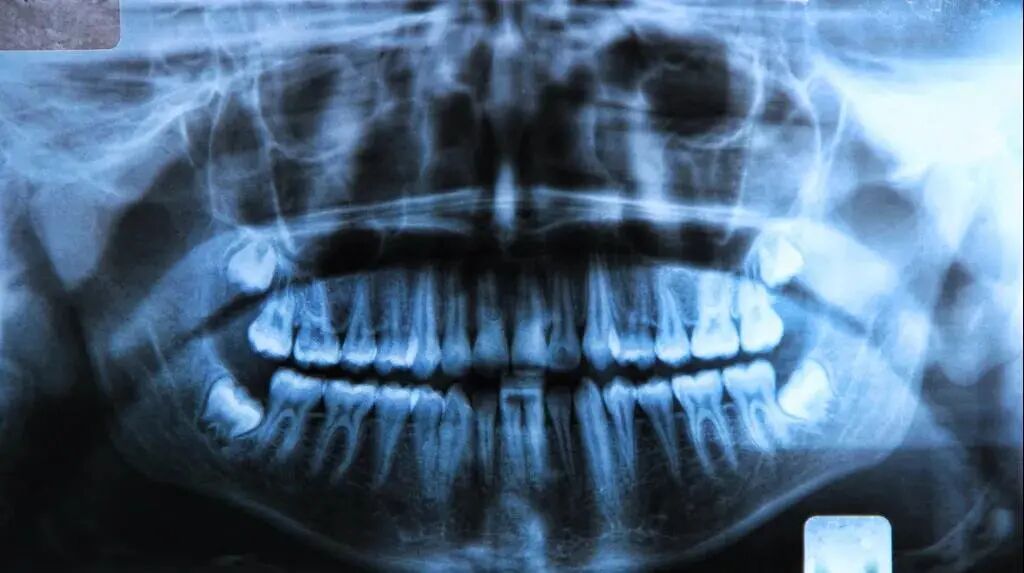

根管充填不密合,未能将整个主根管进行三维严密充填,X片示充填物内或/和充填物与根管壁间有低密度影,是根管治疗失败的主要原因。

有文献统计显示充填不密合约占根管治疗失败病例的45.63%。多数患牙根管形态不佳,未能形成冠方最大、根端最小的连续锥度,而呈圆柱状根管,这种形态的根管无法进行有效的冲洗和严密的充填,根管内易残留细菌等感染物质,造成根管系统的持续或继发感染,导致治疗失败。

欠填,操作长度不准确,致使根预备和充填不到位,最多见于后牙弯曲根管,超填,盲目预备根管或根管充填时未按操作长度操作造成超充。当根管出现欠填,尖周组织液、渗出液可回渗到未充填根管,由于根管内无防御功能,渗出物的分解,微生物的繁殖,即可导致再感染和失败。超填不光导致根尖封闭不全,还可将细菌等感染物质推出根尖孔,引起根尖周炎症。

遗漏根管约占根管治疗失败病例的22.33%。术者对牙齿的解剖结构不熟悉,特别是上颌第二前磨牙及上颌第一磨牙,没有正确阅读X线片,常常造成临床操作时遗漏根管,导致治疗失败。所以,诊断丝偏移投照技术是寻找和确定MB2存在的最好办法,当X线片发现根管影象偏移时,应高度怀疑MB2根管的存在。在临床治疗过程中应进行充分的寻找和治疗MB2根管,提高上颌磨牙根管治疗的成功率。未按医疗操作常规随心所欲的治疗。约占根管治疗失败病例的1%。根管治疗期间的急症(IAE) 是指根管治疗期间的急性反应,主要表现为疼痛和肿胀,临床上IAE 发生率较高,增加了患者的痛苦,使治疗次数增多,是治疗难点之一。这是因为死髓牙根管内有大量的混合细菌感染,同时在预备根管时,由于机械和药物的作用改变了髓腔组织的内环境,可能破坏了根管内细菌之间的共生平衡性,此时细菌及毒素极易通过根管预备进入根尖周组织引起急症,并可作为抗原物质导致免疫反应。封甲醛甲酚( FC)的急症反应明显高于封樟脑苯酚(CP)是由于FC具有较强的细胞毒性和对软组织刺激腐蚀作用,可以引起根尖周组织的坏死和炎症,延缓组织的修复,还可作为半抗原使机体发生免疫反应。下颌牙的急症反应显著高于上颌牙可能是下颌骨骨质较致密,同时重力作用炎性渗出物不易向冠方引流而积于根尖所致。根管侧穿约占根管治疗失败病例的3%。根管侧穿易发生在髓腔的狭窄部和根管弯曲处,主要由于术者对髓腔解剖结构不熟悉,未熟练掌握开髓和根管扩大的方法所致。07根管预备及根管消毒不彻底、充填指征掌握不严格致炎症复发